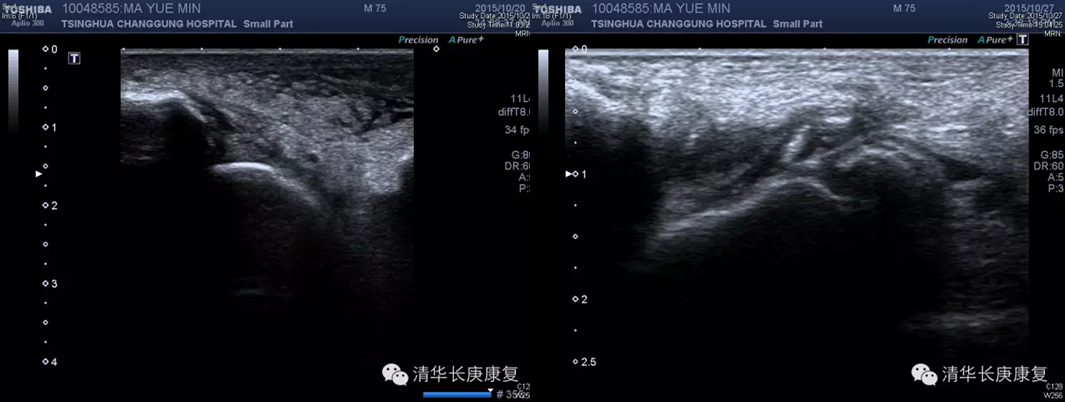

超声引导下右踝关节腔内PRP注射治疗,左图为踝关节超声影像,右图箭头示PRP注射在超声下显像情况